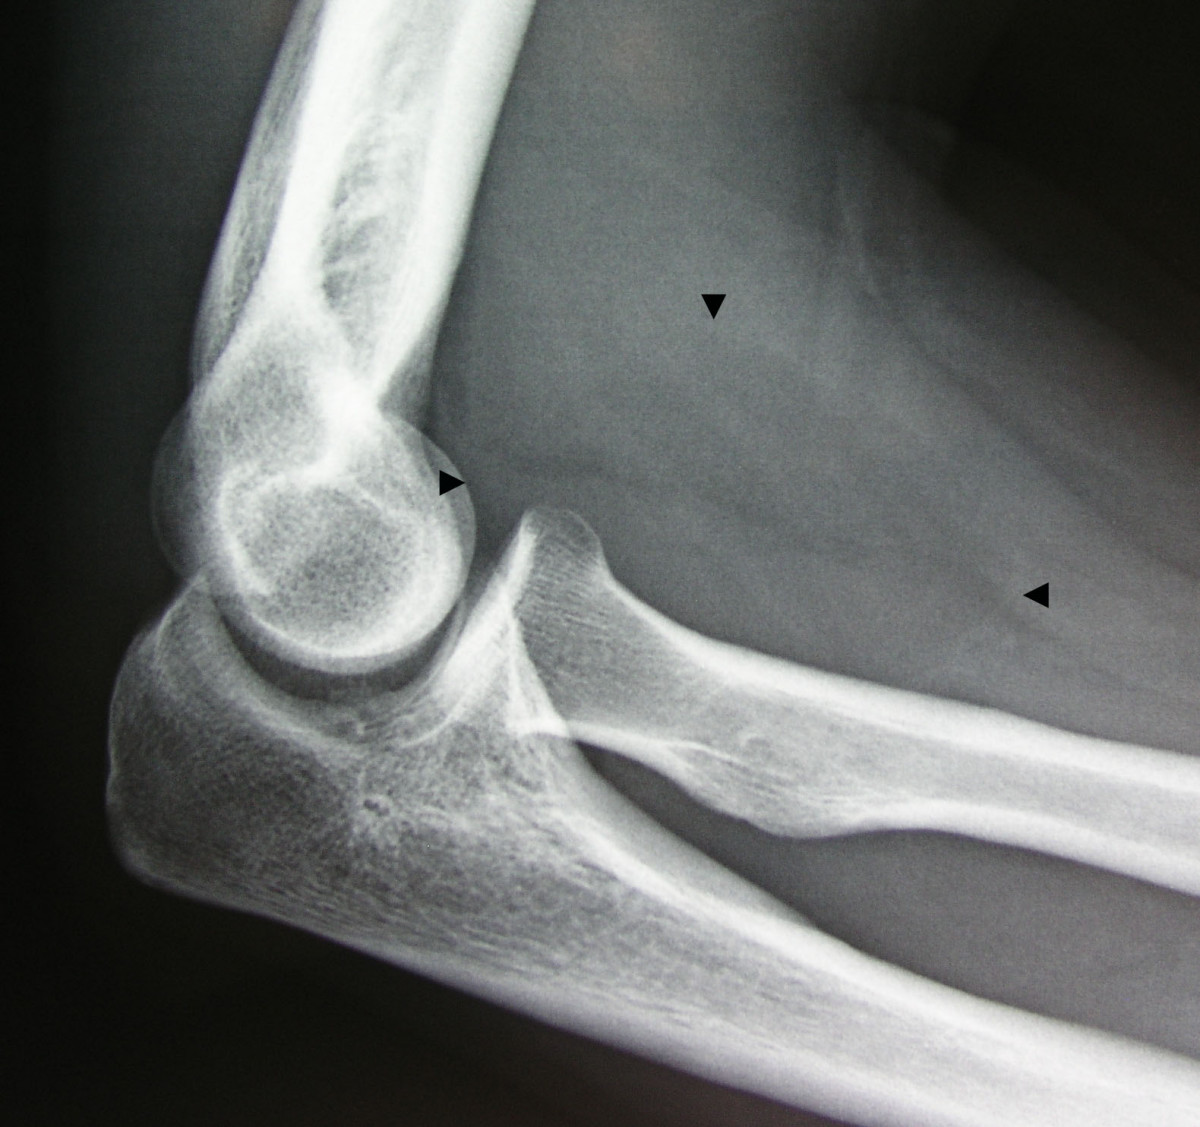

Elbow joint anatomy and examination Source: image.slidesharecdn.com

Elbow joint anatomy and examination